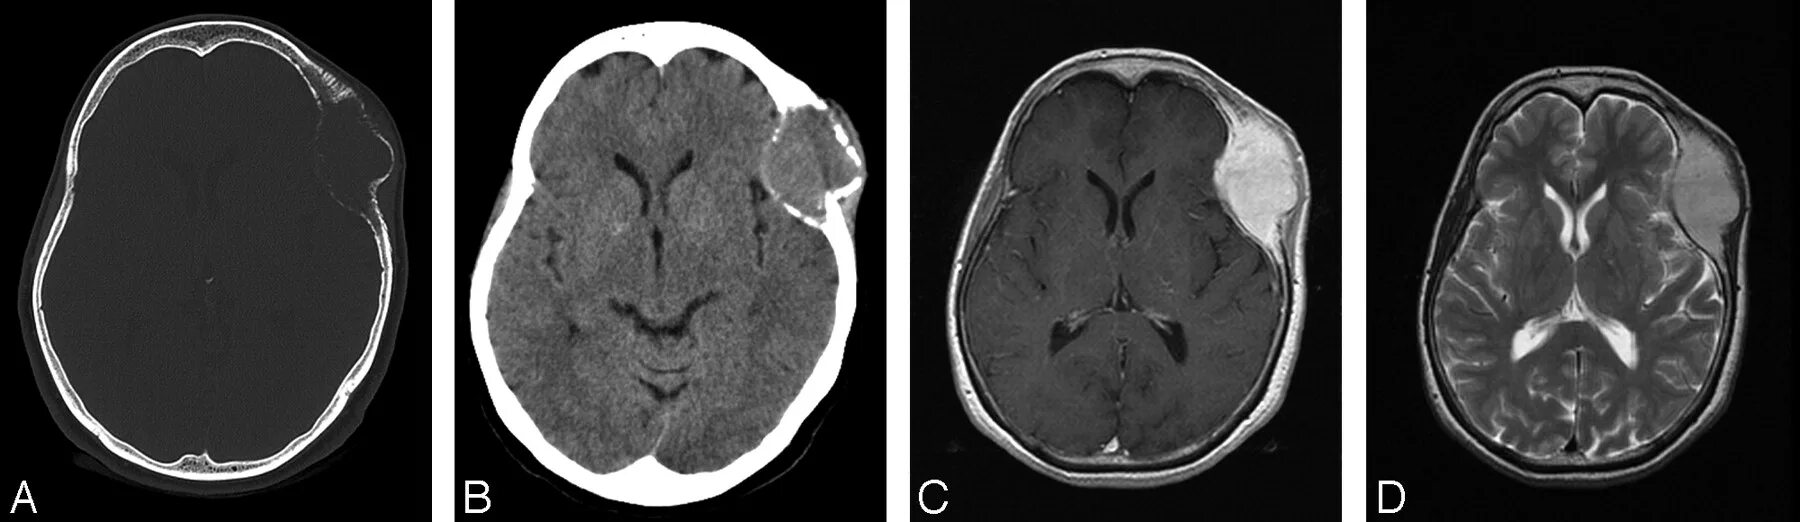

Расширенные субарахноидальные конвекситальные пространства лобных долей